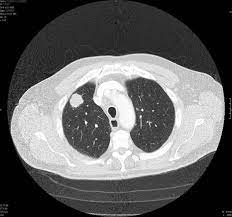

Can You Detect Lung Cancer With Ct Scan : Lung Cancer Snmmi : It can also look at your liver and adrenal glands.. The ct scan might show signs of cancer, but that cancer might not be active for example, it could be scar tissue left over from cancer killed off by your treatment this means you won't know whether or not you need to continue treatment Lung cancer typically goes undetected until it reaches stage 3 or 4. If you are a smoker, it is highly recommended to have a ct scan every 3 months. It can also show whether the cancer has spread outside the lung. But the test is not helpful for light smokers or people who quit smoking more than 15 years ago.

On the other hand, patients who've had surgeries related to their lungs or lung cancer are advised to take more scans than regular smokers. But this kind of testing is for diagnosis and is not the same as screening. It is used to look for early signs of lung cancer. A computer then combines these images into a detailed picture of your lungs. The risk of developing lung cancer due to a single ct scan of the chest is estimated to be one in 10,000.

Thanks to advances in medical technology, a computed tomography (ct) scan now allows doctors to detect lung cancer even during its early stages. The scan only takes a few minutes and is not painful. But this kind of testing is for diagnosis and is not the same as screening. Most doctors do not recommend pet/ct scans for routine follow up of patients after lung cancer treatment. It can also look at your liver and adrenal glands.

Ct scans are very sensitive in detecting lung cancers, and are the most common way in which cancers are diagnosed in the lungs. Need help kicking the tobacco habit? On the other hand, patients who've had surgeries related to their lungs or lung cancer are advised to take more scans than regular smokers. Fundamental to the diagnosis of lung cancer in ct scans is the detection and interpretation of lung nodules. A bone scan can help show if a cancer has spread to the bones. Thanks to advances in medical technology, a computed tomography (ct) scan now allows doctors to detect lung cancer even during its early stages. If the test finds cancer, treatment can start early. This significantly improves patients' chances of recovering from the disease and lowers related treatment costs.